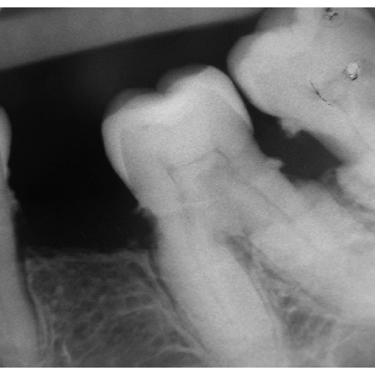

Caries Radicular

La caries radicular es la descomposición del cemento y la dentina en la raíz del diente, común en personas mayores con recesión gingival.

Los pacientes pueden experimentar sensibilidad y dolor en la raíz expuesta.

El tratamiento incluye la eliminación de la caries y la restauración de la raíz. La prevención incluye una buena higiene oral y el uso de flúor.